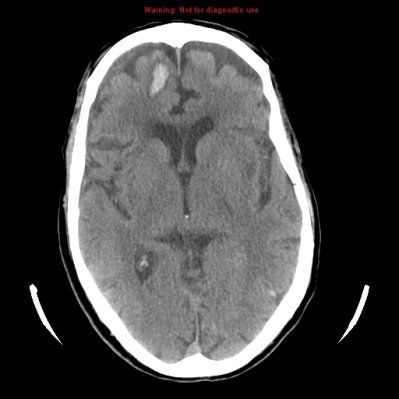

CT scan of a meningioma